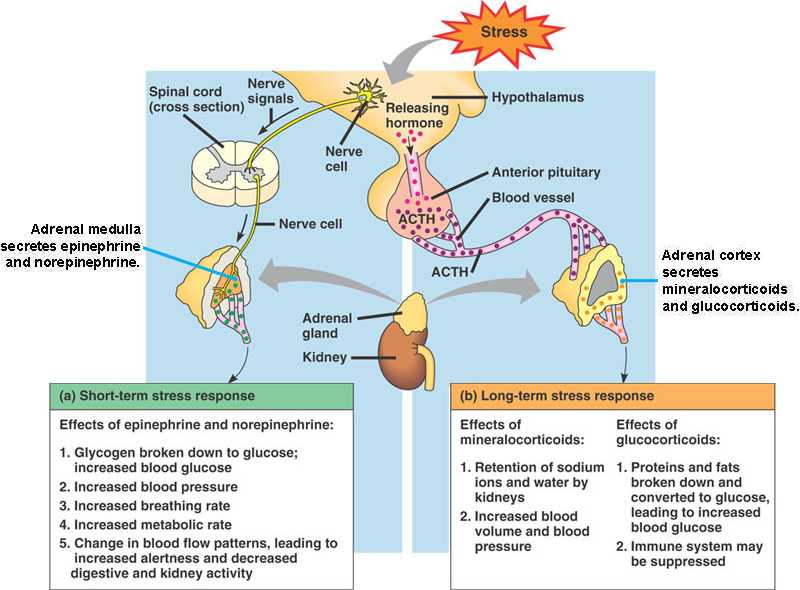

45_13StressAdrenals

45_13StressLong

45_13StressShort

adrenal_cortex.html

epinephrine.html